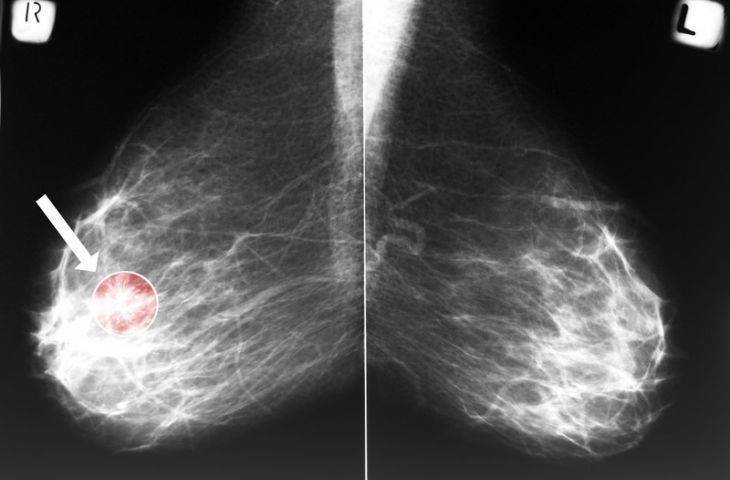

Mamografi Bikin Pasien Kanker Payudara Makin Parah Okezone Lifestyle

Kesesuaian Kategori Bi Rads Mamografi Dengan Pemeriksaan Histopatologi Di Rs Kanker Dharmais Tesis Pdf Download Gratis

Mamografi Nedir

Mamografi Meme Kanseri Riskini Artirir Mi Saglik Haberleri Ntv

Mamografi Nedir Ve Nasil Cekilir Sonuc Nasil Alinir Medicana Saglik Grubu

Bab 2 Ca Mammae